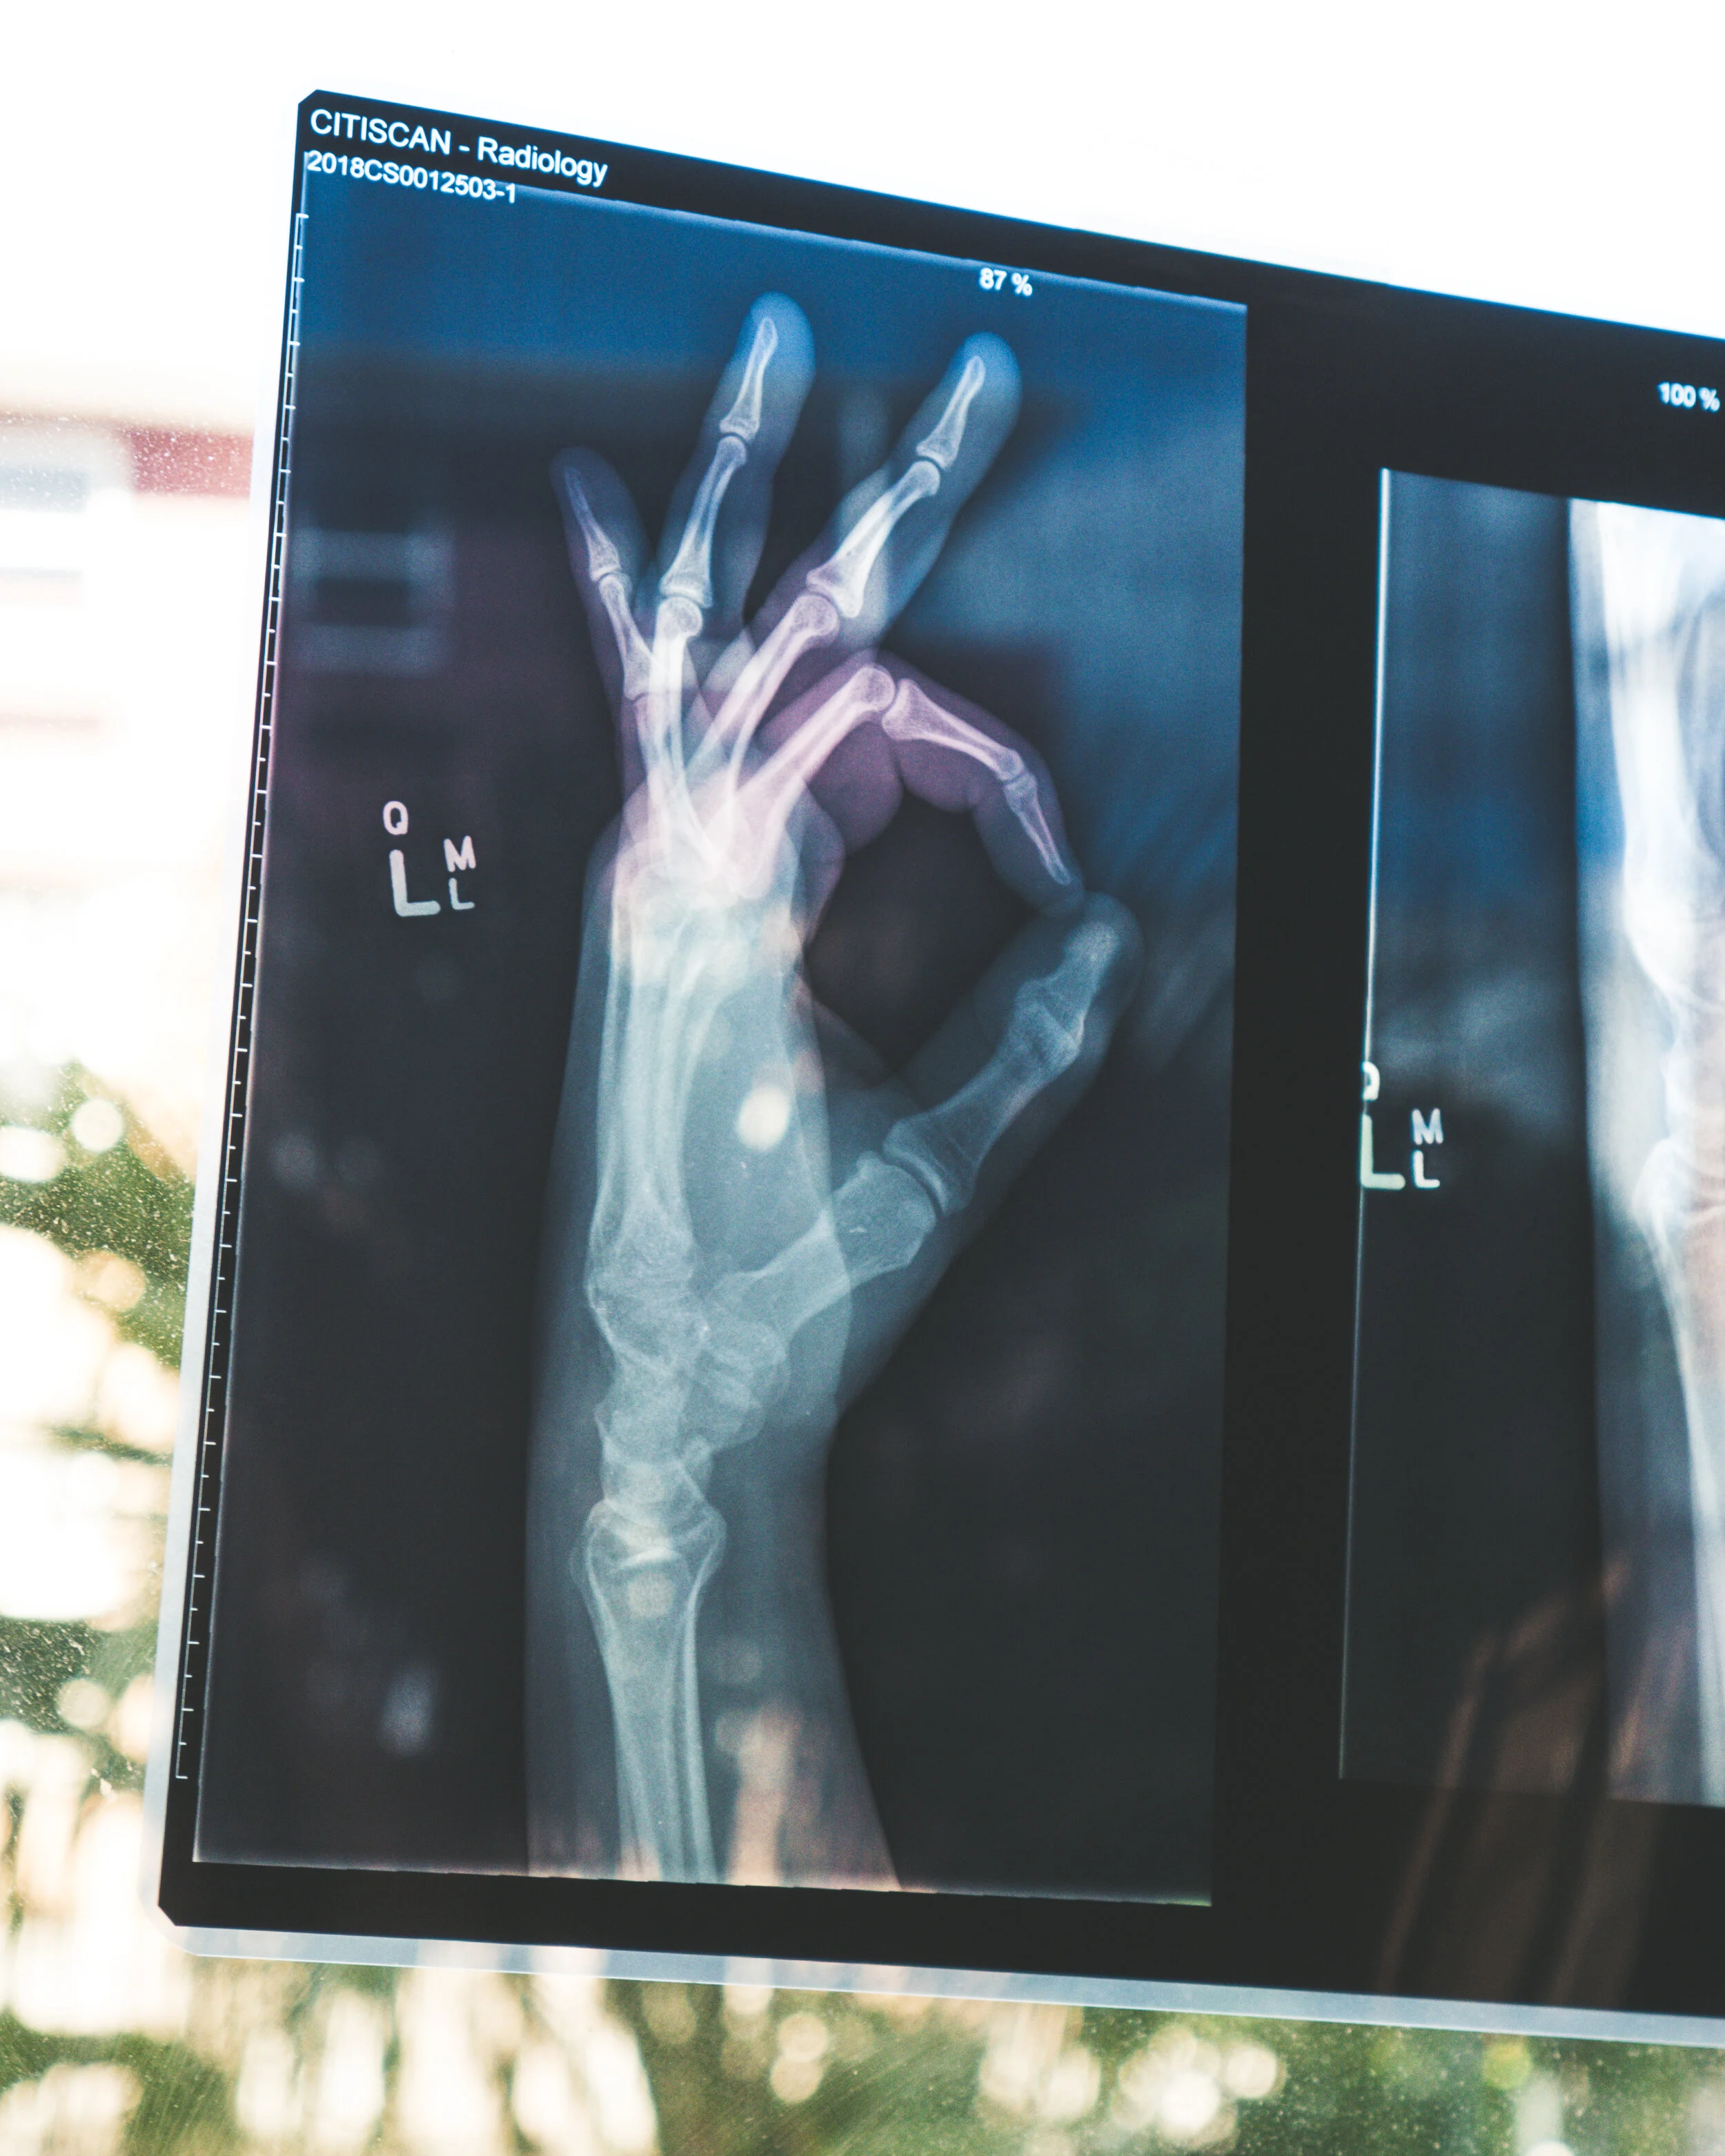

Have you been told or are you concerned that your bones are not as strong as they once were? This can happen when your body is no longer producing new bone cells as effectively as it used to. This means your bones can become brittle, and can be prone to fracture. This can occur throughout the skeleton or be localized to a specific area.

This process is known as Osteoporosis. This bone health condition affects up to 2.2 million Australians! With the condition so common, a question we are regularly asked is “can I improve my bone density and how?”